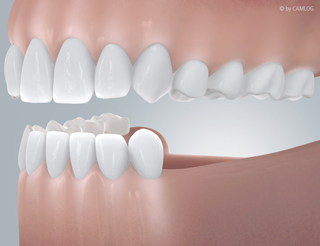

Viele Zähne fehlen

Das Leben hinterlässt Spuren, auch an den Zähnen: Die eine oder andere Lücke wird größer oder ein älterer Zahnersatz führt zu Problemen. Implantate lassen Ihre Zahnreihen wieder völlig unversehrt aussehen. Mit Einzelzahnimplantaten können Sie besonders elegant die ursprüngliche Situation wiederherstellen. Denn jeder Zahn wird separat ersetzt. Fehlen mehrere Zähne nebeneinander, können Sie sich auch für eine implantatgetragene Brücke entscheiden. Egal, welche Lösung Sie bevorzugen, die neuen Zahnwurzeln übernehmen zuverlässig die Aufgaben Ihrer natürlichen Vorgänger. Eine individuell angefertigte Krone oder Brücke schließt jede Lücke passgenau und ästhetisch einwandfrei – ohne Unterschied zu Ihren ursprünglichen Zähnen.

Befund:

Bereits einige Zähne verloren:

Ideale Version

Alle Zähne werden mit je einem Implantat ersetzt.

Alternative Version:

Manche Zähne werden mit einem Implantat ersetzt.